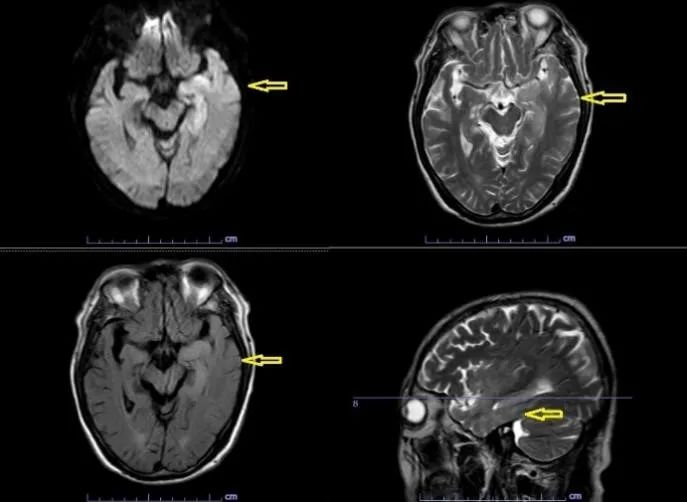

1月12日,北京华信医院(清华大学第一附属医院)神经内科监护室收治了一名发热10天,伴精神行为异常5天的老年患者。入院当天患者淡漠木僵、言语不能,全身可见散在出血点。经头部核磁共振显示左侧岛颞叶与海马区异常信号;脑电图显示额颞区慢波,左侧额颞区及蝶骨电极较多尖波、尖型慢波散发,偶可波及左半球。初步诊断:症状性癫痫(继发性癫痫)、脑炎。立即完善腰椎穿刺,脑脊液宏基因组测序提示I型单纯疱疹病毒感染。给予抗癫痫、抗病毒、脱水降颅压等对症治疗。